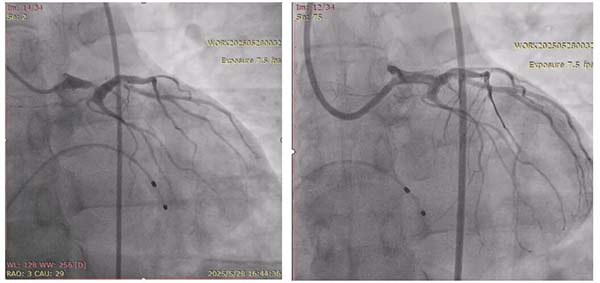

术前左主干重度狭窄(左)PCI术后冠脉造影(右)